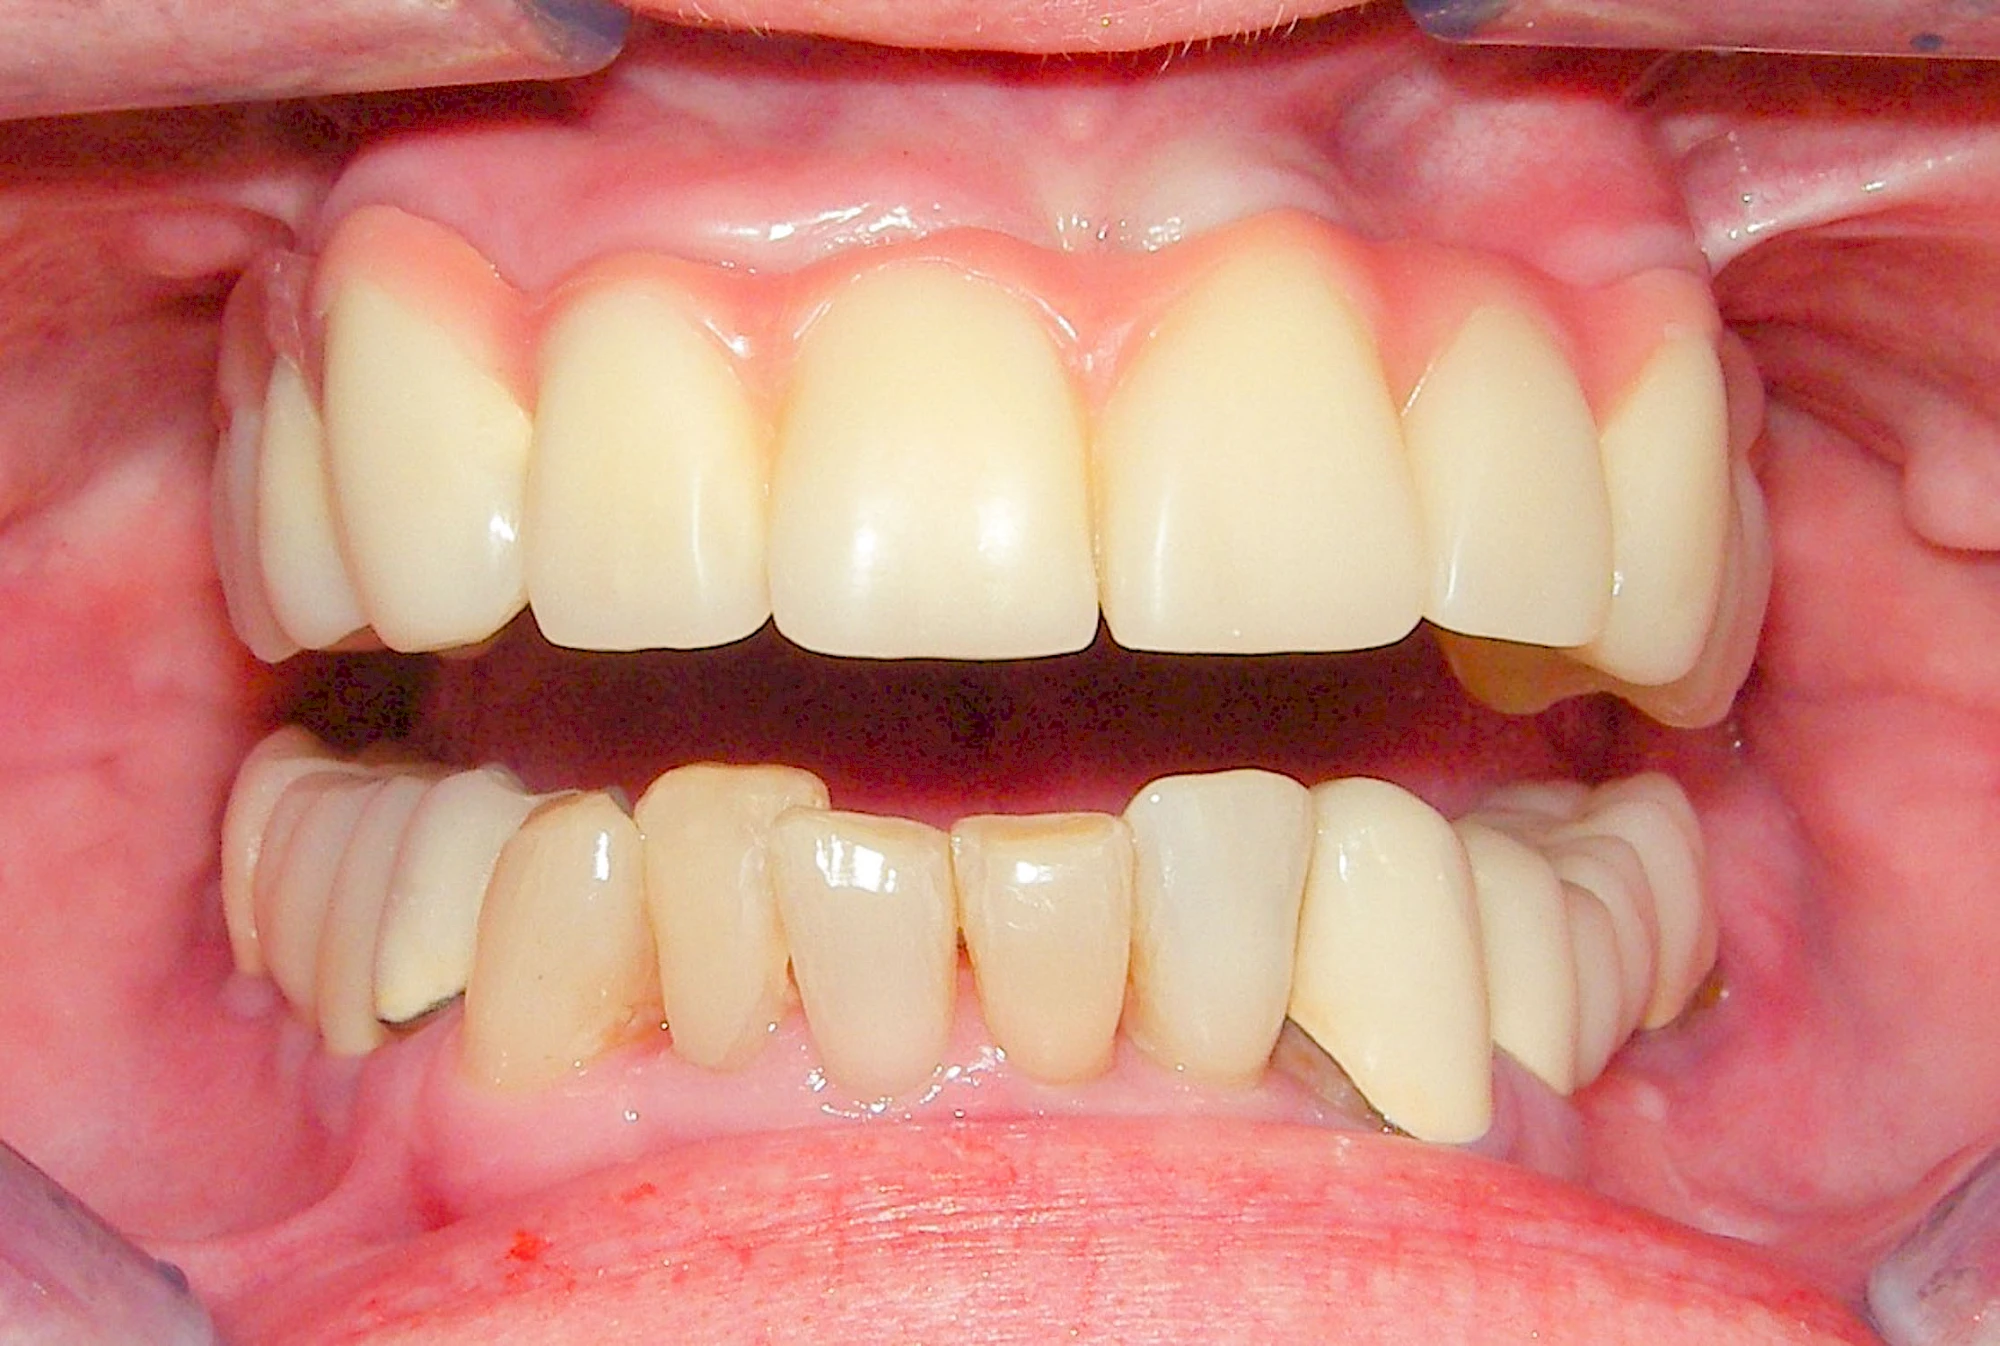

Fehlen einzelne Zähne und die Nachbarzähne sind unbeschadet oder gut zahnärztlich versorgt, werden immer häufiger Implantate gewählt, um die Lücken zu schließen. Auch bei größeren oder verteilten Lücken, wenn keine herausnehmbare Prothese gewünscht ist, werden Implantate für Kronen- bzw. Brückenversorgungen gesetzt. In Einzelfällen entscheiden sich sogar zahnlose Patienten für eine festsitzende Versorgung auf Implantaten.

Varianten zur Verankerung von festsitzendem Zahnersatz auf Implantaten